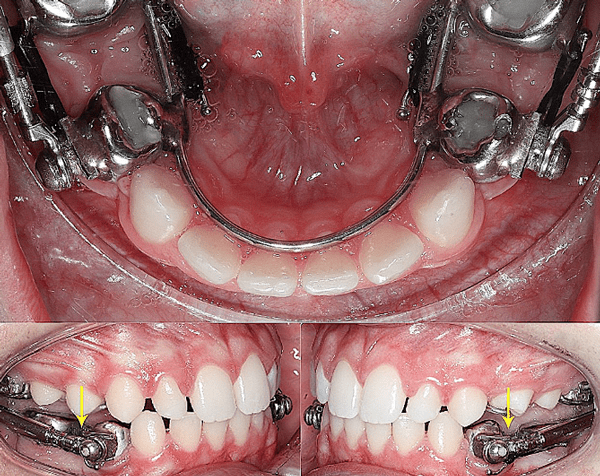

قبل و بعد ارتودنسی فک پایین

درمان ارتودنسی ممکن است برای اصلاح مشکلات فک پایین در شرایط خاص کافی باشد، در درجه اول زمانی که ناهماهنگی شدید نیست و شامل ناهماهنگیهای اسکلتی قابل توجهی نمیشود اما در ناهماهنگیهای قابل توجه اسکلتی زمانی که فک پایین به طور قابل توجهی در مقایسه با فک بالا بیرونزدگی یا عقبنشینی داشته باشد، باید هر دو فک تحت درمان قرار بگیرند.